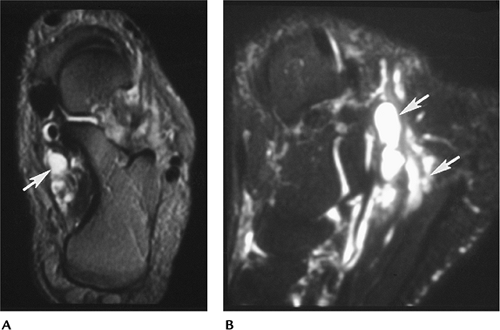

FIGURE 6-60 Enlarged veins causing tarsal tunnel syndrome. Axial (A) and sagittal (B) fat-suppressed T2-weighted images showing dilated veins or varices in the tarsal tunnel (arrows).